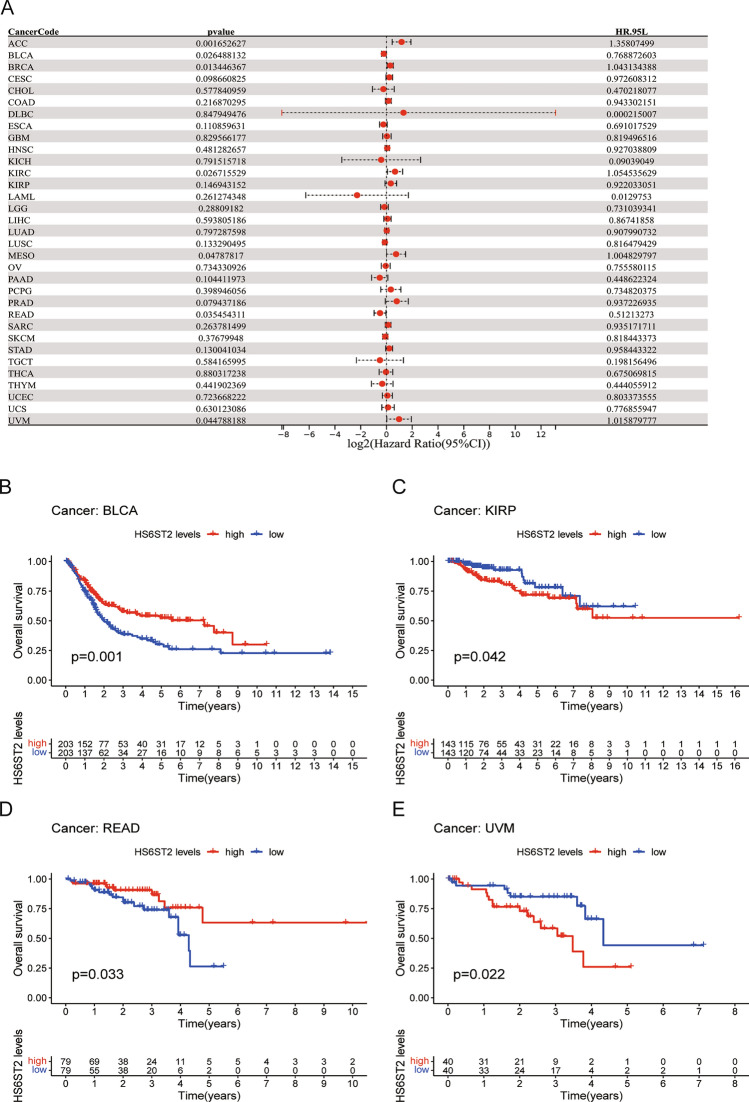

Prognostic significance of HS6ST2

Via the TCGA database, we examined the value of HS6ST2 mRNA expression for predicting OS, DFI, DSS, and PFI across cancers. Cox regression analysis revealed that low HS6ST2 expression was connected with poorer OS in breast invasive carcinoma, mesothelioma, kidney renal clear cell carcinoma, uveal melanoma, and adrenocortical carcinoma but associated with better OS in rectum adenocarcinoma and bladder urothelial carcinoma (Fig. 3A). As determined by KM OS analysis, HS6ST2 was a protective factor for patients with bladder urothelial carcinoma and rectum adenocarcinoma but a risk factor for patients with kidney renal papillary cell carcinoma and uveal melanoma (Fig. 3B–E). We also determined the correlation between the expression of HS6ST2 and the DFS rate in 33 different cancers. HS6ST2 was found to be a protective factor in bladder urothelial carcinoma and a risk factor in kidney renal papillary cell carcinoma, stomach adenocarcinoma, adrenocortical carcinoma, and according to Cox regression analyses (Fig. 4A). Similarly, KM analysis of DSS uncovered that HS6ST2 was a risk factor in stomach adenocarcinoma, kidney renal papillary cell carcinoma, and uveal melanoma but acted as a protective factor in bladder urothelial carcinoma (Fig. 4B–E).